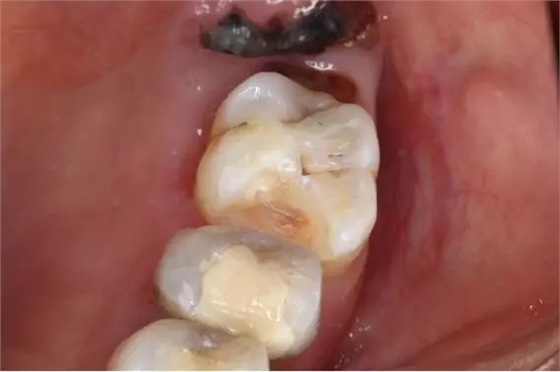

17.成品

椅旁修復病例的完成,給文彬口腔門診部的患者都帶來不一樣的體驗,提高了效率的同時也節(jié)省患者的時間。數(shù)字化是未來的趨勢,即刻修復一定會越做越多,越做越好。